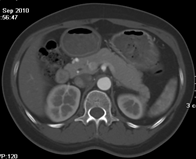

如上圖所示,相鄰的三張軸位圖像未見明顯異常,根據(jù)傳統(tǒng)軸位圖像很難得到準確的臨床診斷。

同一病人利用容積數(shù)據(jù)進行三維處理后,高品質(zhì)MPR和三維圖像上則清晰顯示了縱向排列的腹腔干與腸系膜上動脈相鄰近,血管發(fā)生變 異,近端血管閉塞,為臨床提供了精確的診斷信息。